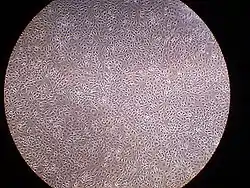

A layer of mesothelial cells grown in cell culture, featuring the typical "cobblestone" appearance | |